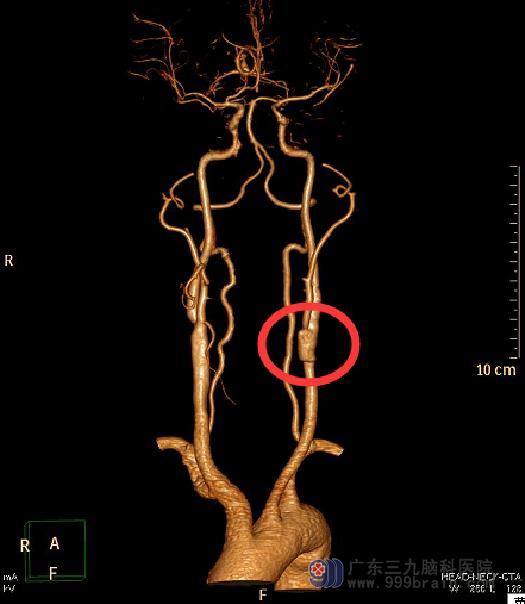

广东三九脑科医院头颅CTA检查提示:左侧颈内动脉颈段起始部局部狭窄闭塞;左侧颈外动脉起始部明显狭窄,狭窄面积约65.5%。全脑血管造影显示:1、左侧颈内动脉起始部闭塞,主要由左侧颈外动脉脑膜中动脉、左侧椎动脉肌支-枕动脉-颈内动脉代偿供血;2、左侧椎动脉起始重度狭窄,狭窄程度约62%,狭窄长度约3mm;3、左侧颈外动脉重度狭窄,狭窄程度约70%,狭窄长度约5mm;4、右侧颈内动脉起始部小斑块形成。

由综合神经外科鲁明主任主刀,在全麻下行左侧颈内动脉粥样斑块取出+内膜剥脱术,术中见颈内动脉起始段黄白色粥样斑块,质硬,边界清,长度约5cm,予取出斑块,剥除内膜,连续缝合颈内动脉切口,手术过程很顺利。术后陈老师语言功能明显改善。复查头颅CTA提示:左侧颈内动脉颈段起始部原狭窄闭塞段现管腔通畅,较邻近管腔较宽。